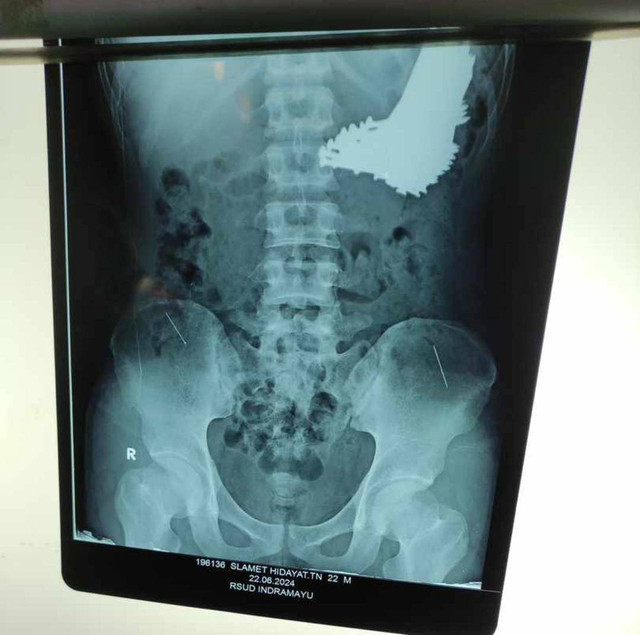

"Tim dokter kemudian melakukan pemeriksaan. Dari hasil rontgen, terlihat ada benda asing di dalam lambung yang diduga adalah paku," ujar Direktur RSUD Indramayu, Dr. Deden Bonni Koswara, pada Minggu (23/6/2024).

Kemudian, tim dokter bedah RSUD Indramayu yang dipimpin oleh Dr. Rahmat Sp.B langsung melakukan operasi pada Sabtu (22/6/2024).

"Operasi dimulai sekitar pukul 1 dan selesai pukul 3, terdapat 70 paku yang ditemukan, paku reng atau paku besi," ujar Deden.